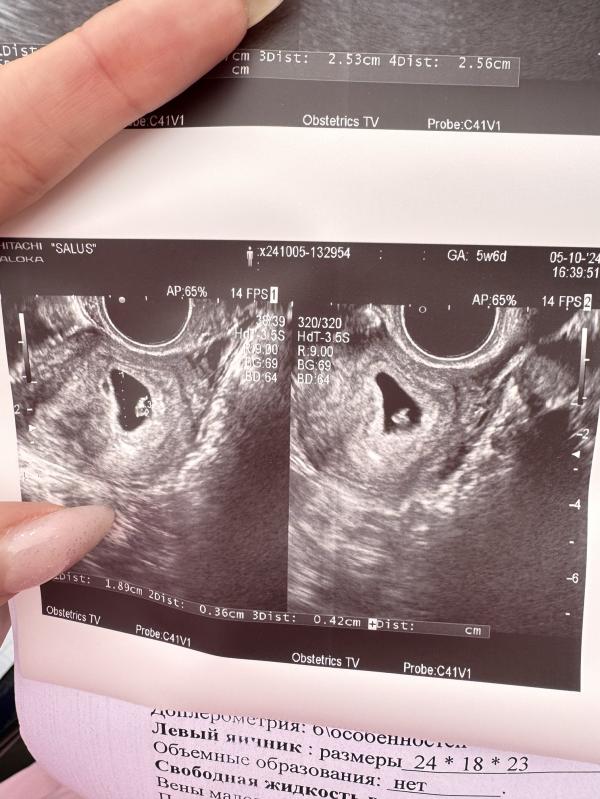

Сходила ,сегодня на УЗИ,по месячным 6 недель 1 день,по УЗИ сказали 4-5 мм,сказали сердцебиение есть .Это нормально?

Может просто зависит от учреждения и врача,она мне сказала все хорошо,живой и растет .Проблем никаких нет.В прошлую беременность ходила в этот же срок ,по УЗИ было 5.6 недель и там не было ничего слышно,мне сказали через 10 дней прийти еще .А здесь хорошо,по фото УЗИ,эмбриончики отличаются,так что я думаю что все хорошо

Тогда почему не написали ЧСС? У меня в 7 недель в заключении было указано ЧСС 96 уд и +- такие же параметры( поздняя овуляция), а у вас просто СБ+